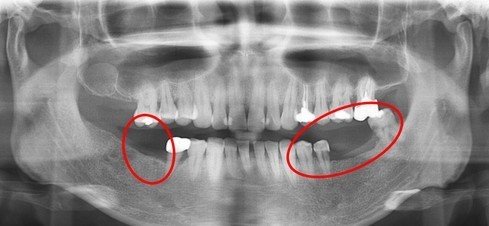

如果不注重牙齿健康,蛀牙可能会导致一颗牙脱落,发展成牙周病一整排牙齿就会相继脱落。越来越多患者,年纪轻轻就要面临半口、乃至全口牙齿缺失。不管是外貌、咀嚼功能还是身体健康,都受到影响。那么,多颗牙齿缺失该怎么办?河南省专业正规口腔医院

针对多颗牙缺失,目前比较理想的办法就是种植牙来改善。固定义齿的应用范围较多地受到客观条件的限制,而活动义齿又因不能充分恢复咀嚼效率、影响发音及有异物感而难以令患者满意。

种植牙能够帮助恢复牙齿的咀嚼功能,同时还能够避免其它牙齿出现不健康的现象。种植牙能够对植入部位的骨组织形成功能性刺激,延缓牙槽骨的吸收,使缺失牙的修复基本恢复原来的功能和完美的外观,成为真正的美容修复体。修复后戴用舒适、无异物感。它属于当今口腔医学精尖技术,被誉为人类的“第三副牙齿”。